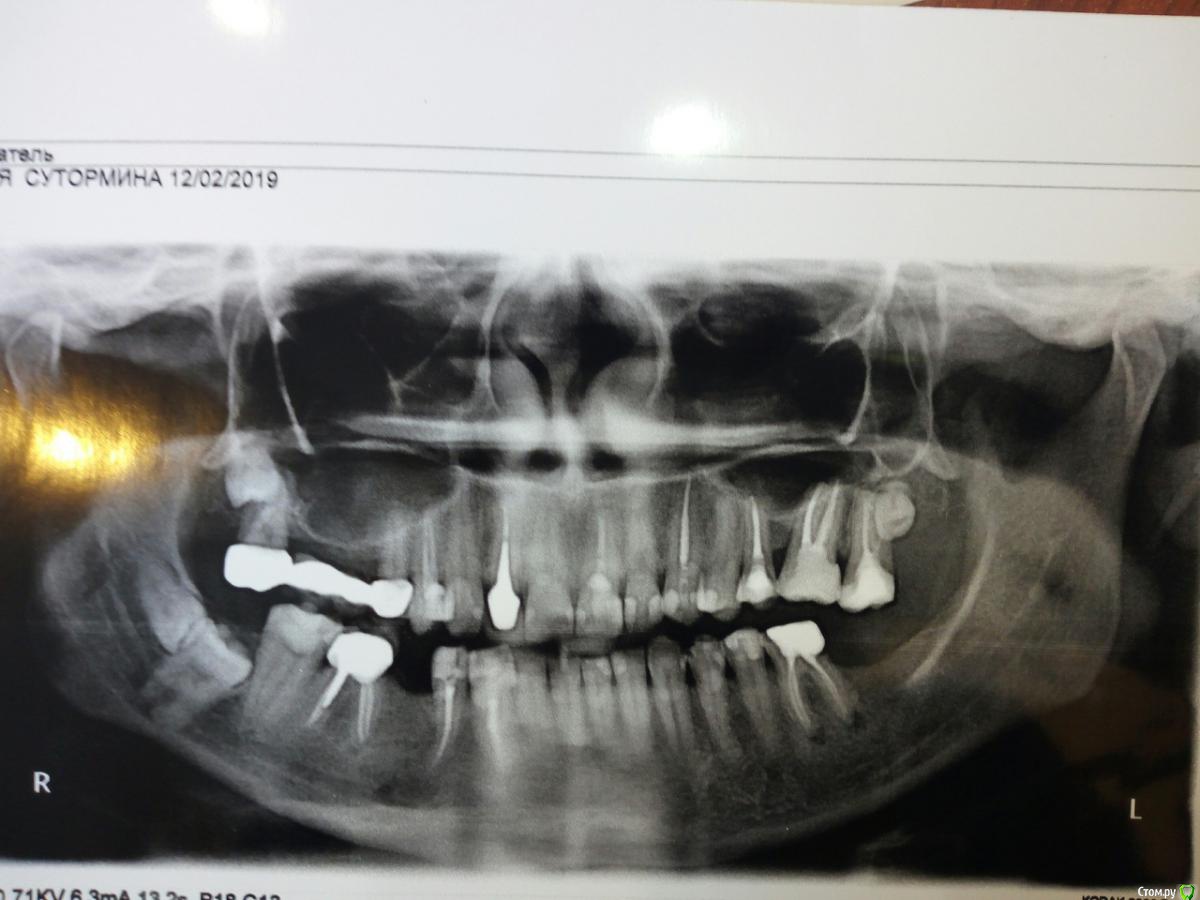

Plades Опубликовано 5 марта, 2019 Поделиться Опубликовано 5 марта, 2019 Имеются четыре ретинированных зуба: три "девятки" и одна "восьмерка". Есть ли в моём конкретном случае показания к их удалению? Или риски выше, чем нынешняя необходимость? Что делать: ждать или заранее удалить их все? Если да, то каким способом? Ссылка на комментарий

___49___ Опубликовано 5 марта, 2019 Поделиться Опубликовано 5 марта, 2019 а мне уже почти 39 лет в этом возрасте ростковая зона зуба закрыта, и он не растет . Если не беспокоит - не трогайте. Область 48\49 желательно выполнить КТ - не совсем ясная картина по ОПТГ . 1 Ссылка на комментарий